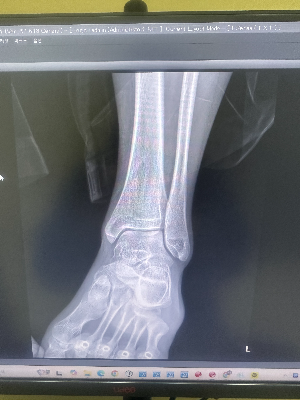

아까 엑스레이 찍기 싫다며 칭얼대던 그 남학생, 결과가 어떻게 나왔을까요? 본인은 뼈가 안 부러졌다고 호언장담하더니, 막상 모니터에 사진을 띄워보니 찢어진 인대가 뼛조각을 물고 떨어져 나간 '견열 골절'이 명확하게 보였습니다. 진료실에서 반깁스 처방을 받고 휠체어를 타고 나오며 *"선생님, 엑스레이 안 찍고 그냥 파스만 붙였으면 큰일 날 뻔했어요!"*라며 머쓱하게 웃고 가더라고요.

방사선사가 환자분의 발목을 안쪽으로 약 15~20도 정도 살짝 비틀어서 찍는 사진입니다. 발목뼈(거골)는 정강이뼈와 종아리뼈 사이에 마치 'ㄷ'자 모양의 장붓구멍(Mortise)처럼 쏙 들어가 맞물려 있습니다. 발목을 살짝 안으로 돌려야만 이 세 뼈 사이의 간격이 겹치지 않고 가장 명확하게 드러납니다.

인대가 파열되어 관절이 불안정해지면, 이 '모티스' 간격이 정상보다 넓어지거나 한쪽으로 쏠리게 됩니다. 즉, 인대 자체는 안 보여도 뼈와 뼈 사이가 벌어진 간격을 통해 '아, 인대가 끊어져서 뼈를 제대로 못 잡아주고 있구나!'라는 결정적인 단서를 잡아내는 것입니다.